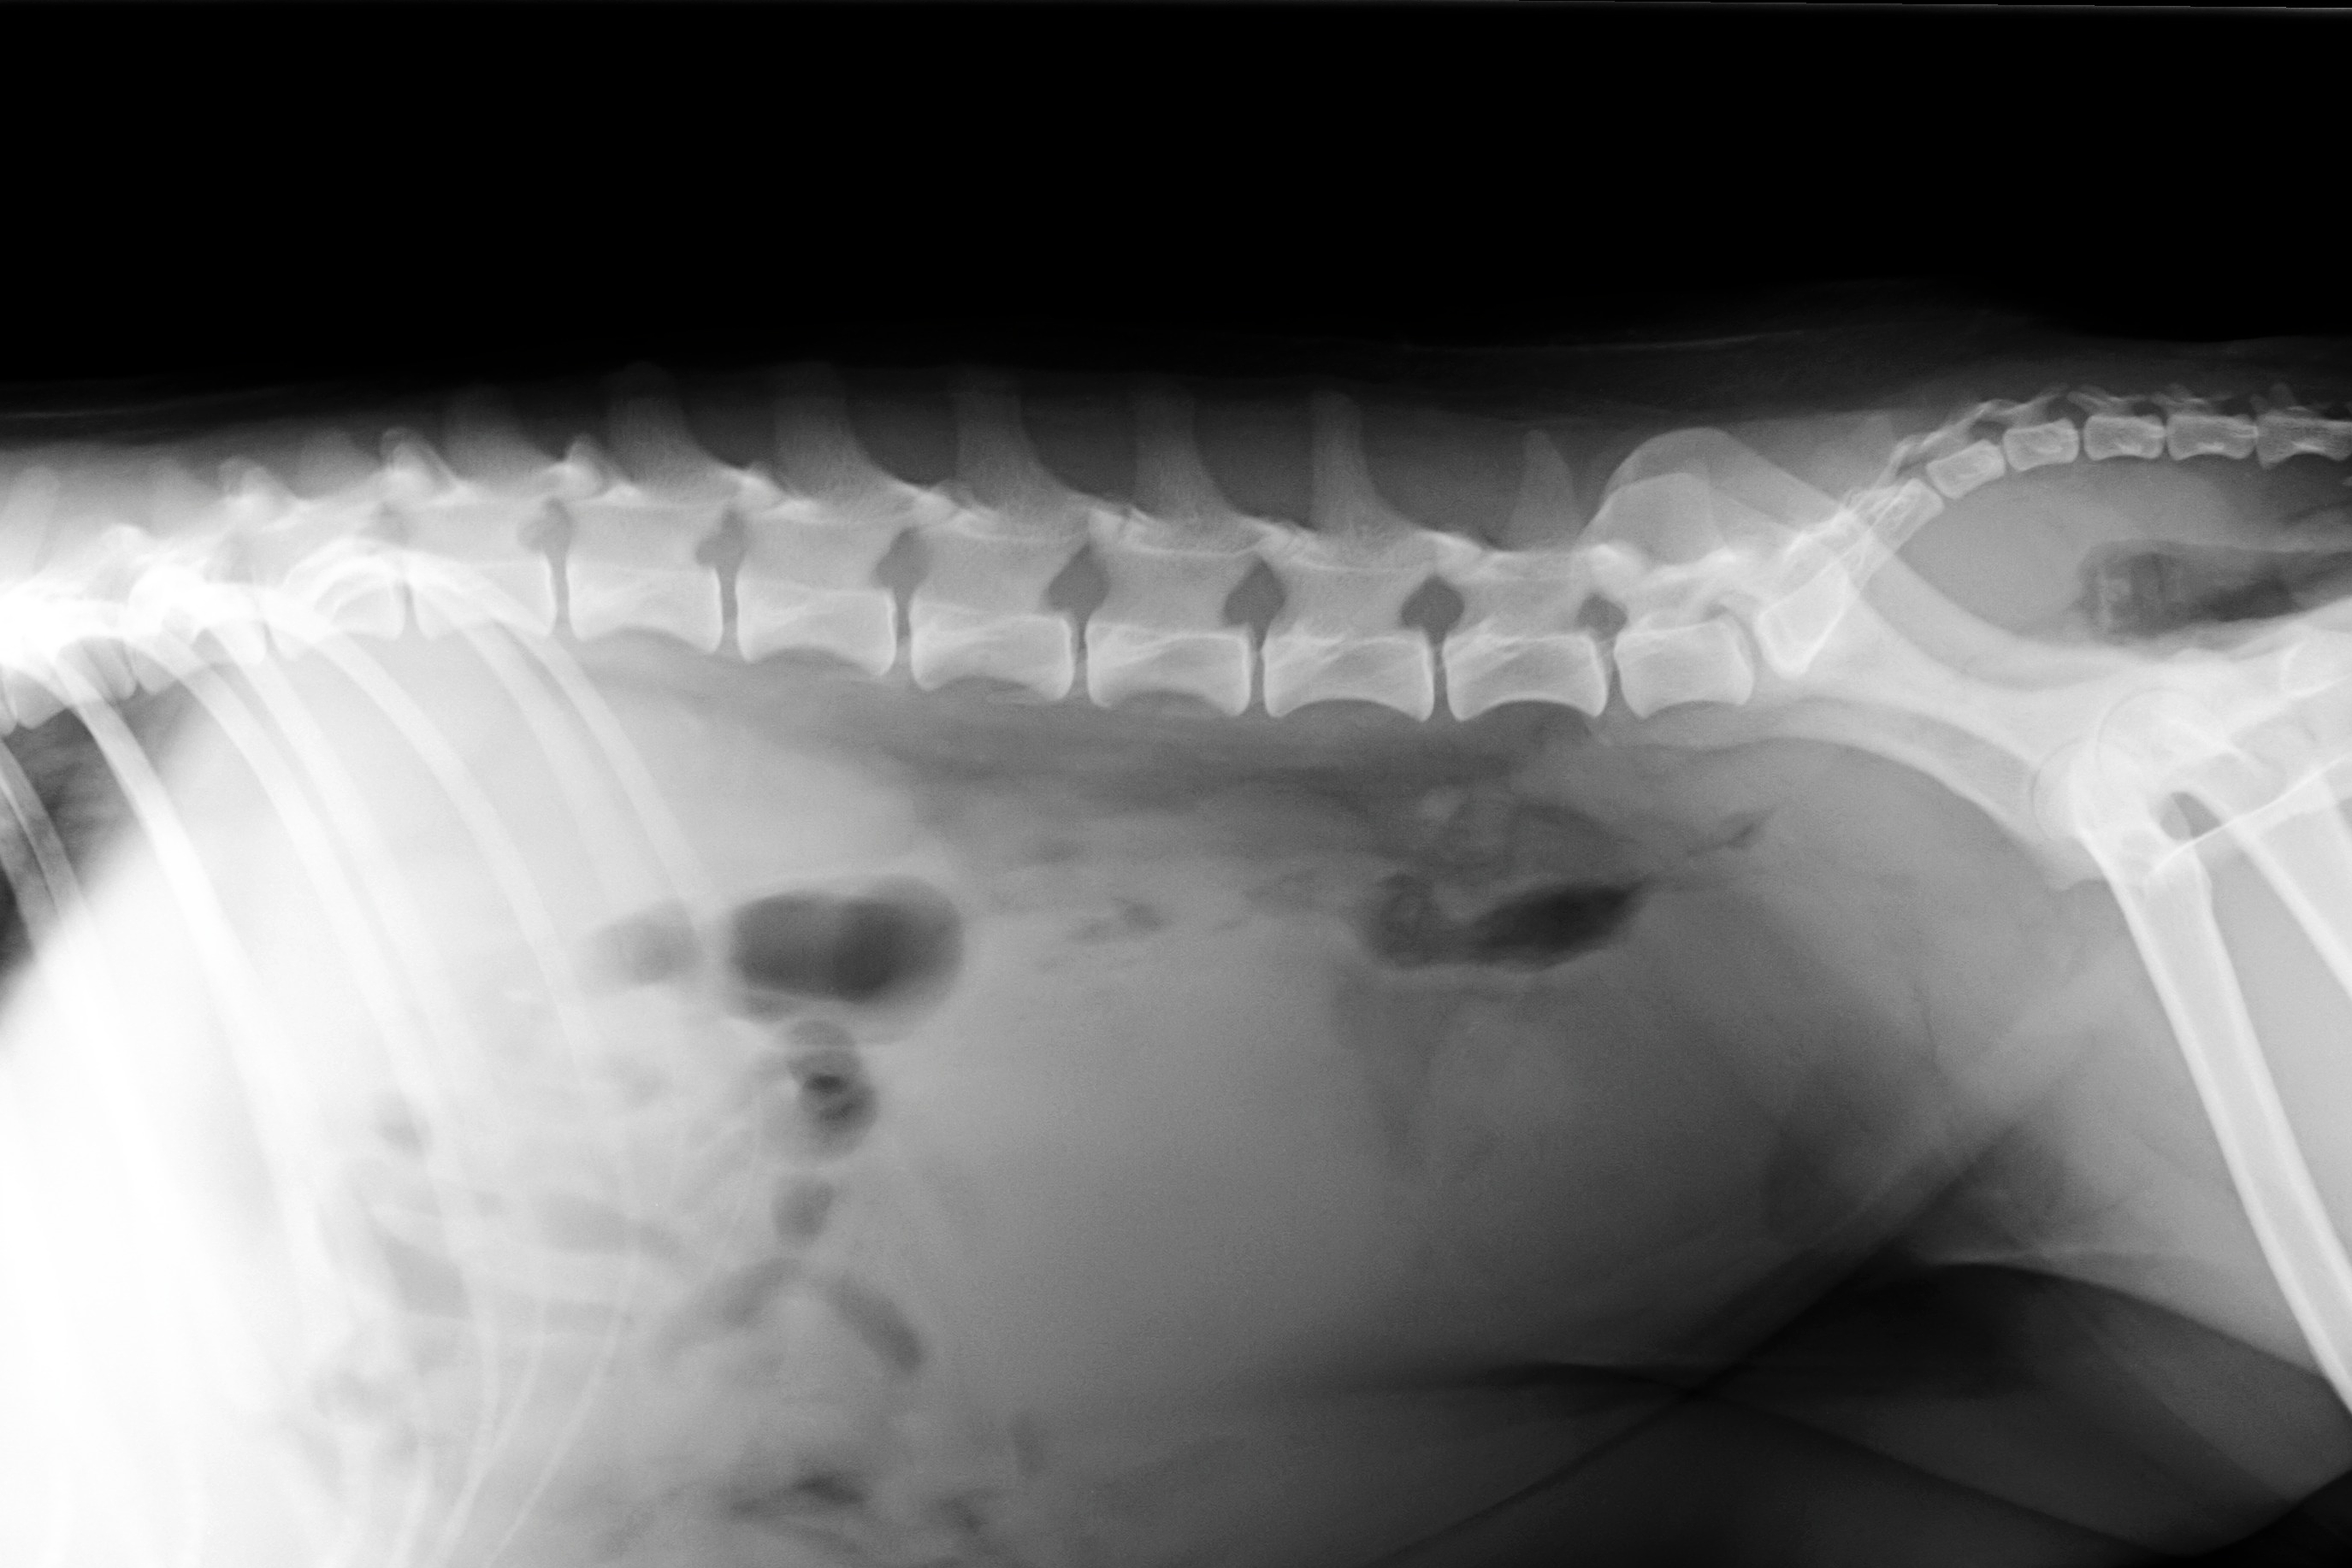

(5) 7 měsíců lat

(5) typ 3 páteř VD